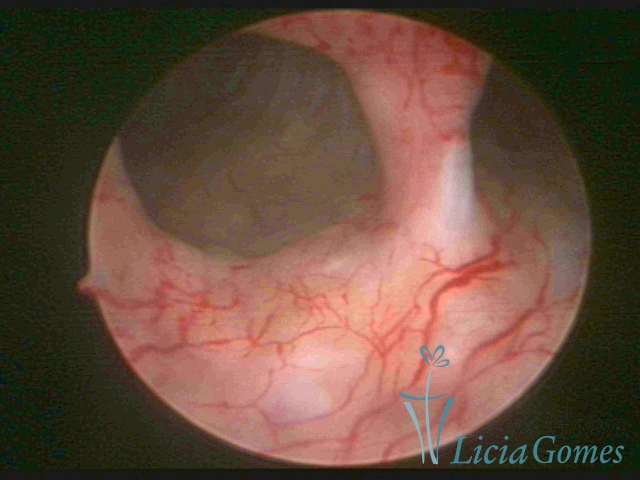

Septate uterus

It probably occurs by the lack of resorption on the middle line, in the merge of Müllerian ducts. The uterus is divided by a partial or total septum which is viewed as a crossbar, not covered by endometrium, which not bleeds when sectioned.

Complete septum when it occupies the whole extension of the cavity, dividing it into two hemicavities.

When this septum occupies only a part of the extension of the uterine cavity, it is considered as incomplete.